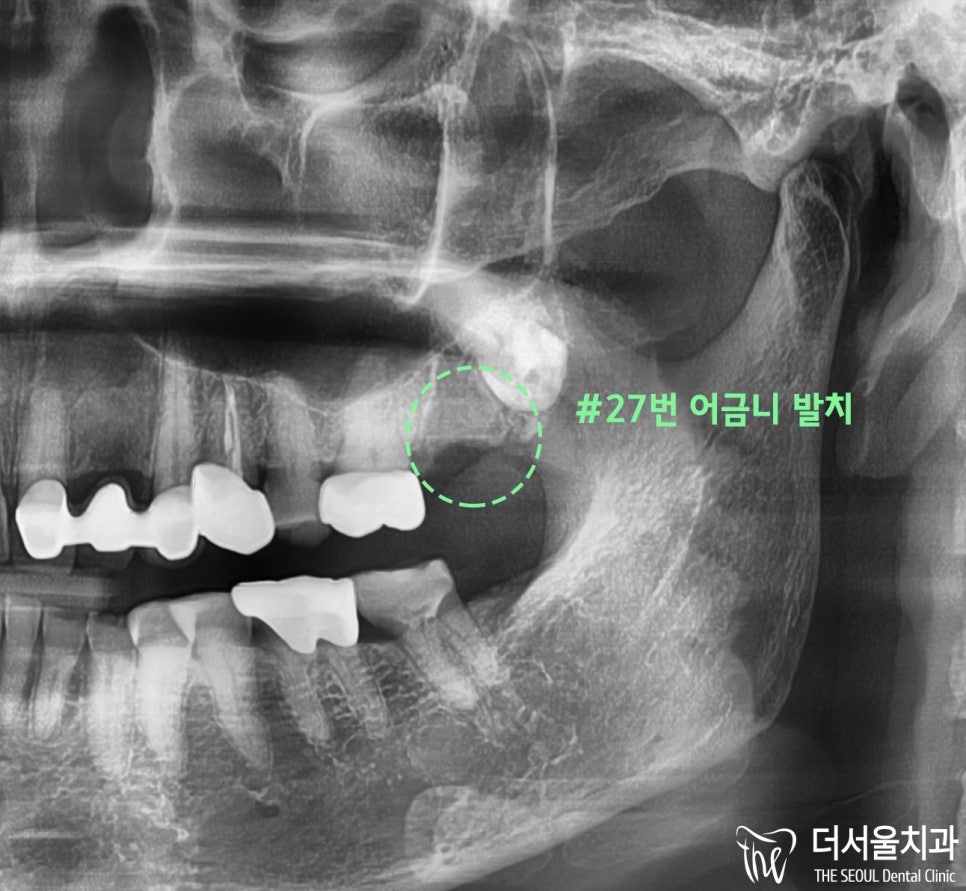

#27번 발치 후

파노라마 사진을 보여드리겠습니다.

주변 부위 손상 없이

#27번 어금니를 깔끔하게 뽑았습니다.